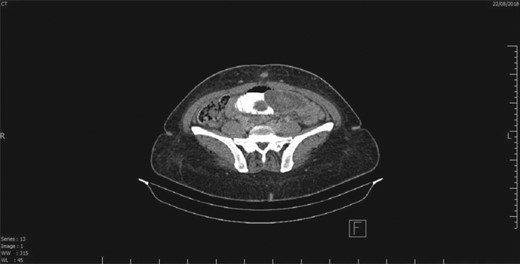

Intussuscepted gangrenous part of the small intestine after reduction of intussusception.

This is a case of a 46-year-old female, 3 years post REYGB. She presented to the emergency department with sudden abdominal pain as well as nausea and vomiting, which started the day before presentation (30 minutes post prandial). Moreover, on physical examination, the abdomen was soft with pain out of proportion (severe pain with minimal tenderness) and no other signs of peritoneal irritation. Furthermore, laboratory data were unremarkable. Abdominal computed tomography (CT) revealed a long segment of obstructed retrograde small bowel obstruction adjacent to the jejuno-jejunal anastomosis associated with a complete proximal small bowel obstruction (Fig. 1). Therefore, the patient was immediately taken to the operating room, and laparoscopic exploration of the abdomen was performed. A segment of retrograde jejuno-jejunal intussusception was encountered with dilated small bowel proximal to the intussusception and a collapsed part distal to it. Decision was made to convert the procedure to an open surgery through a small midline laparotomy (Fig. 2), and a trial was performed to undo the intussusception. There was a gangrenous segment of about 23 cm, necessitating resection and anastomosis (Fig. 3). The anastomosis was performed using a gastrointestinal anastomosis stapler device. Consequently, the patient tolerated the procedure well, and she was sent for recovery in a good condition. Pathology confirmed a gangrenous jejunal segment with features consistent with external venous compression (intussusception related) with viable surgical resection margins. Afterwards, the patient was discharged on postoperative day 3 in a good condition, and she remained asymptomatic during the follow-up period of 1 year.